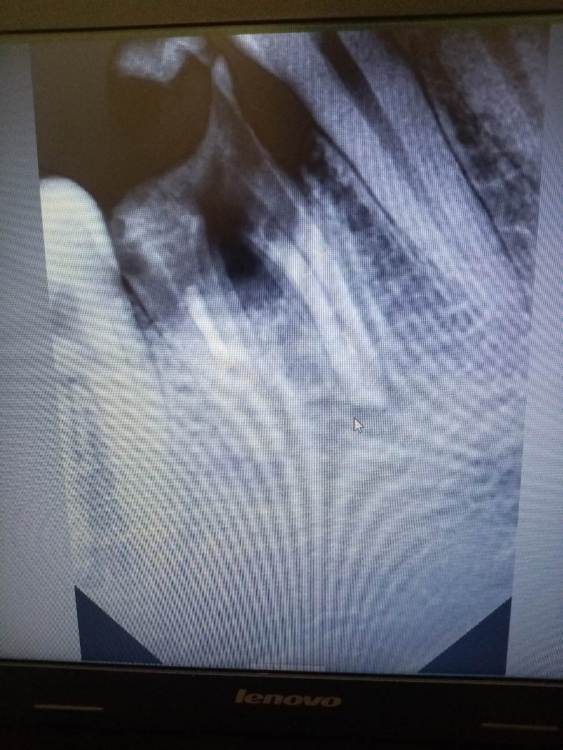

Зуб разрушен уже 7 лет. Врач сказал, что корни разрушены, восстановить их нельзя. Только удаление. Снизился уровень костной ткани из-за атрофии. Скажите, есть хоть какой то шанс сохранить зуб культевой вкладкой? Сохранить корни и установить на них коронку. Может быть, нарастить атрофированную костную ткань.

IMG_20240126_182401.jpg